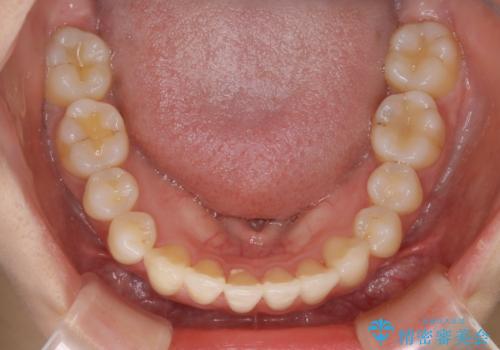

マイクロインプラントとIPR

歯を並べるスペースを作るために、歯の遠心移動と歯列の拡大、歯自体を少しだけ小さく削る(IPR)という方法を複合的に組み合わせて配列を行いました。遠心移動用のゴムかけにはマイクロインプラントという小さいネジを用いて骨に直接固定源を求めました。